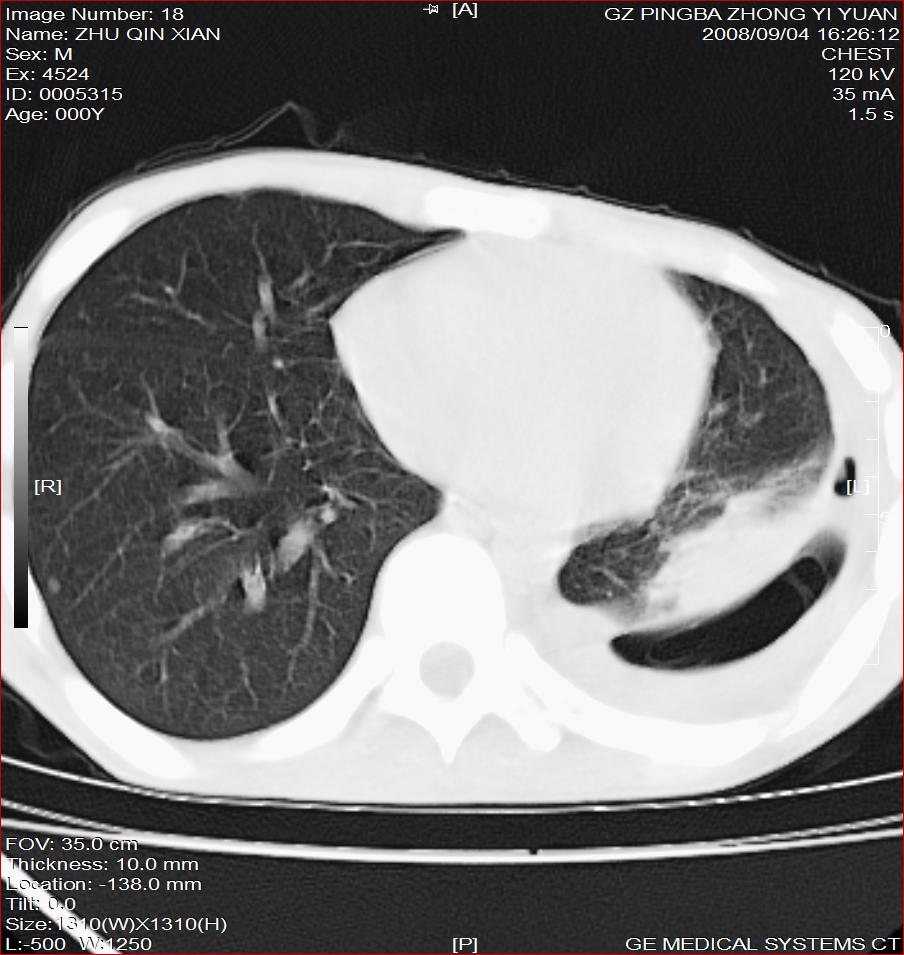

以下是引用随光逐影在2008-9-4 20:05:00的发言:[br]1)考虑两肺结核。2)左侧胸膜炎(胸膜肥厚、粘连,胸腔积液)。3)左侧局限性气胸。

以下是引用子十在2008-9-4 19:34:00的发言:[br]左上肺结核并空洞及双肺播散。节段性肺不张、胸腔积液、胸膜肥厚粘连。[br]